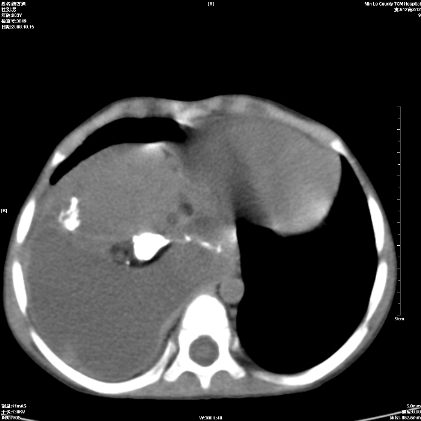

标题: PED1609:男性,3岁。彩超示肝Ca. [打印本页]

标题: PED1609:男性,3岁。彩超示肝Ca.

考虑后纵隔恶性畸胎瘤伴肝内多发转移可能性大,右侧肾上腺转移不除外.

3岁;肝低密度灶;有钙化;有转移灶;考虑肝母细胞瘤;查afp

考虑神经母细胞瘤并肝转移

考虑:1、右侧后下纵隔畸胎瘤。

2、肝脏多发血管内皮细胞瘤。

建议:增强确诊。